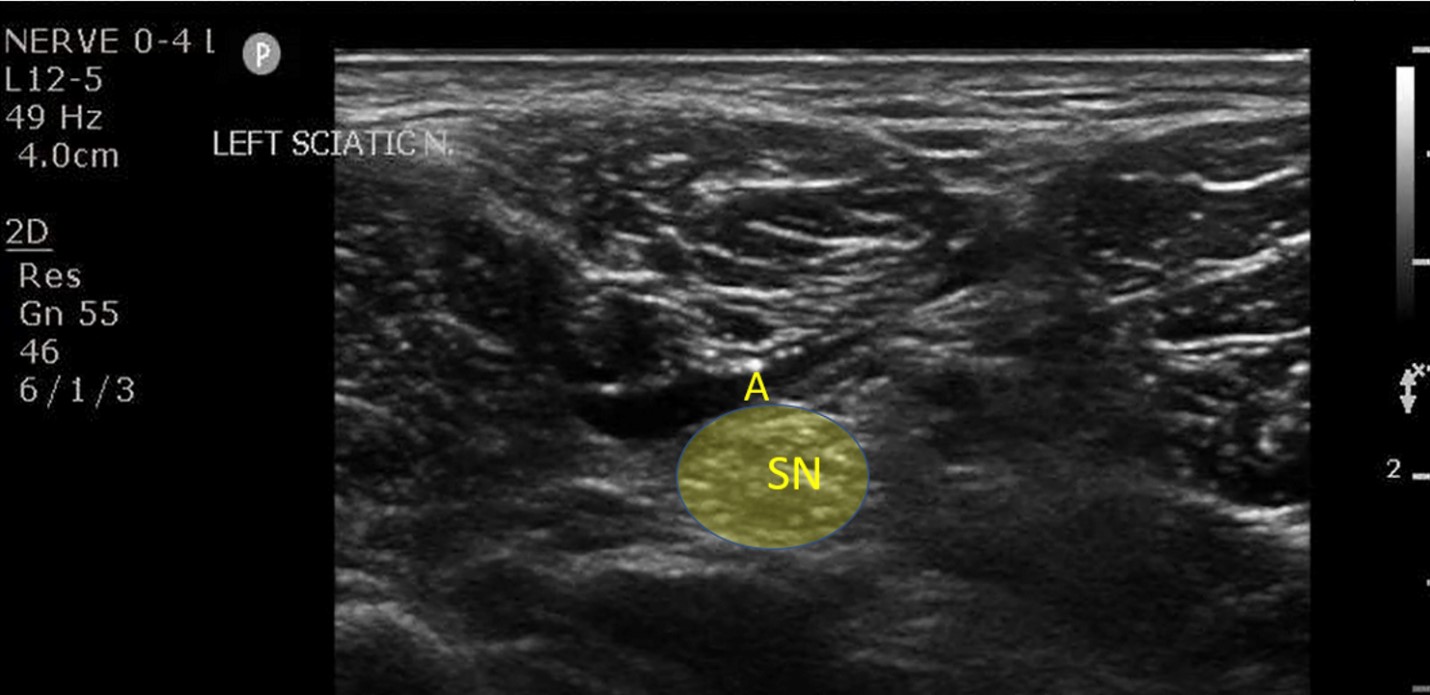

While in the emergency department, a popliteal sciatic nerve block was performed (Figure 2) for reduction and splinting of the fracture. The patient reported a pain scale of 6 out of 10 prior to the nerve block, and after the nerve block, it was reduced to 1 out of 10. He did not require procedural sedation for the reduction procedure and tolerated the procedure well. The patient was admitted to the orthopedic service for operative management.

The ultrasound settings should be optimized for nerve visualization and the gain and the dynamic range set for needle tip visualization. The depth should be set at about 3-4cm and, prior to beginning the procedure, the nerves (shallow) and the vessels (deep) must be identified. The nerves have a honeycomb appearance and vessels will be anechoic. Color Doppler may be used to identify the popliteal artery and vein. The sciatic nerve should be identified above the popliteal crease. While the ultrasound probe is in the transverse position, the probe can be moved caudally to identify the sciatic nerve bifurcating into the TN and CPN. As it was mentioned above, an in-plane approach is preferable with the needle entering from the lateral side. The needle positioning may be identified by direct visualization, by secondary indentation, or by the presence of reverberation artifact. It is important as with all nerve blocks to maintain constant visualization of the needle tip as it is advanced toward Vloka’s sheath. To aid in puncturing through Vloka’s sheath and avoiding intraneural injection, the needle tip should target the space between the TN and CPN.

Next, draw back on the syringe prior to injecting the anesthetic to ensure the needle tip is not within a vessel. Finally, 15-20mL of local anesthetic is required to bathe the sheath that envelops the TN and CPN.